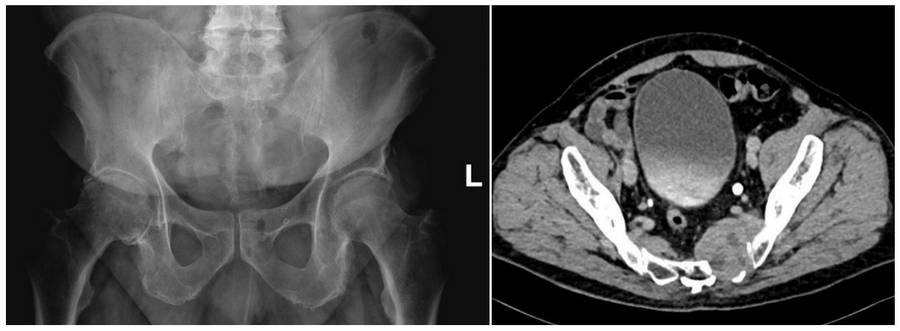

Before the surgery: X-rays and CT scans show damage to the left side of the sacrum.